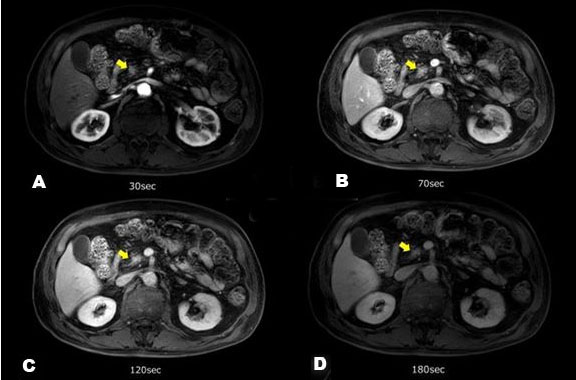

We conducted 3-T contrast-enhanced MRI which revealed a low-intensity mass of approximately 1 cm in the pancreatic head on T1-weighted images and on T2 fat suppression; it was recognized as a tumor, exhibiting clearer high-intensity than did the adipose tissue (Figure 5). In addition, the lesion showed high intensity on diffusion-weighted imaging (DWI) and low intensity on the apparent diffusion coefficient (ADC), indicating that pancreatic cancer was present in the pancreatic head. Gadolinium-enhanced MRI (Figure 6) revealed that the mass was late-enhanced, and we were able to make a definitive diagnosis of pancreatic cancer. Endoscopic retrograde pancreatography (ERP) and magnetic resonance cholangiopancreatography (MRCP) (Figure 7) confirmed disruption of the main pancreatic duct and dilation of the pancreatic duct. Serial pancreatic juice aspiration cytological examination (SPACE) was performed. After performing endoscopic nasopancreatic drainage and pancreatic duct brush cytology, pancreatic juice was collected thrice via a pancreatic catheter. Cytopathology revealed class IIIa disease (Papanicolaou classification). Based on the imaging test results, the patient was confidently diagnosed with pancreatic cancer (T1c, N0, M0, stage IA), and we decided to perform pancreaticoduodenectomy as treatment.

Figure 6: Thirty-second (A), 70-s (B), 120-s (C), and 180-s (D) gadolinium-enhanced MRIs (magnetic resonance imaging) are shown. A mass (yellow arrow) clearly showing a late-onset contrast-enhancing effect in the head of the pancreas.